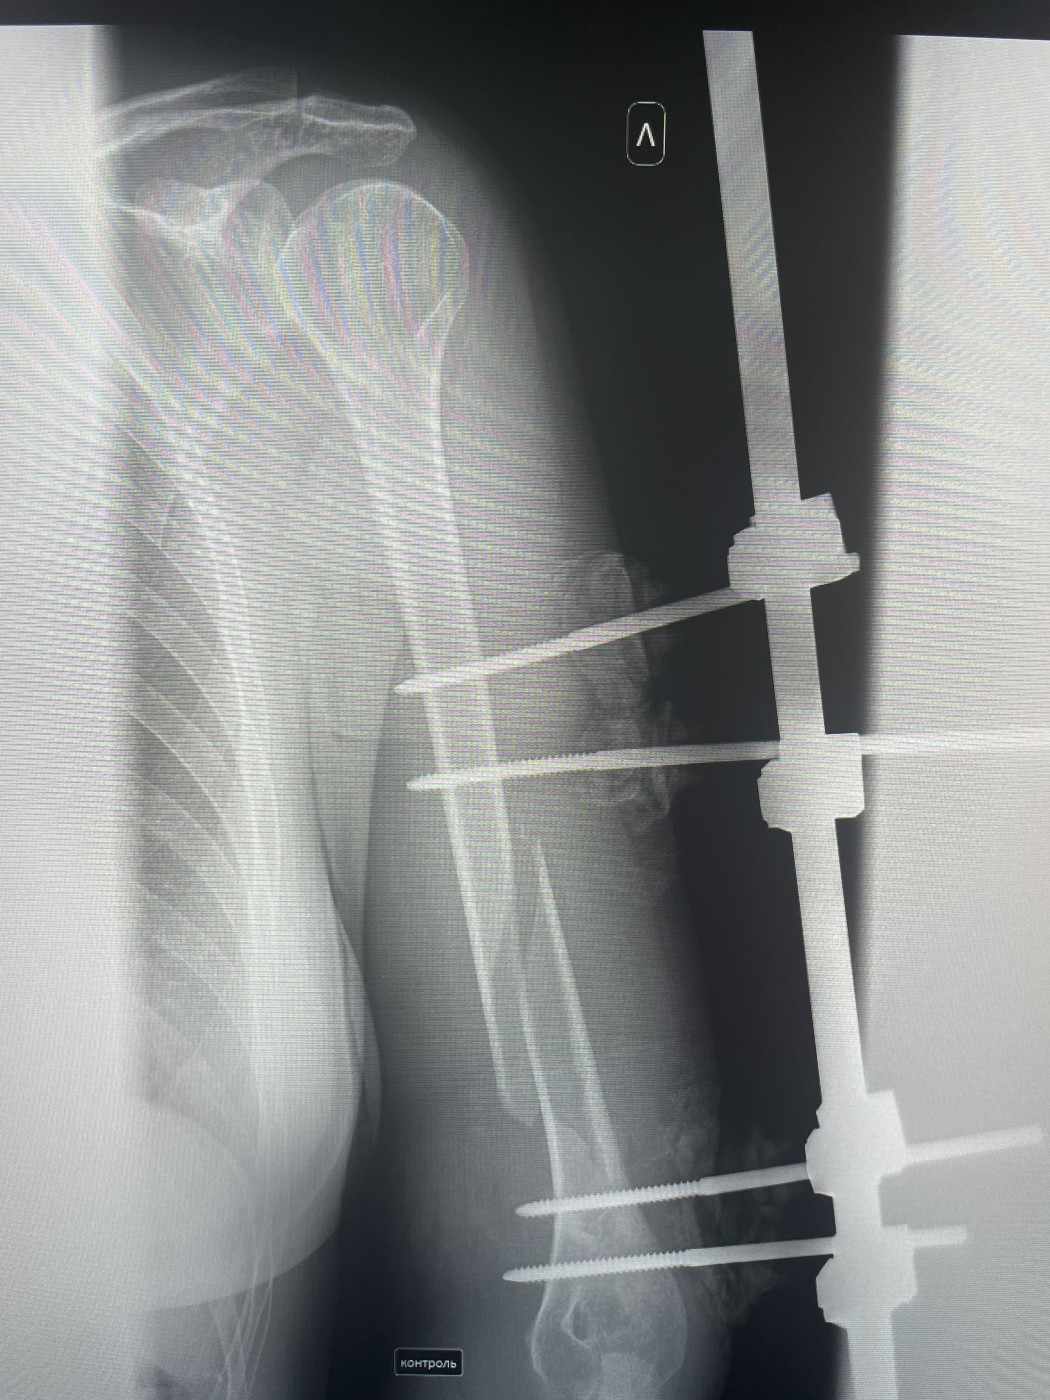

Аппарат Илизарова: принцип работы и применение

Раздел: Моменты озарения